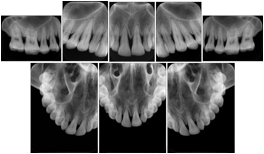

Intra-oral radiography typically involves acquisition of multiple images of various parts of the dentition. Many digital radiographic systems offer customized templates that are used for displaying the images in a study on the screen. These templates may also be referred to as mounts or view sets. The Structured Display Object represents a standard method of encoding and exchanging the layout and intended display of Structured Displays. A structured display object created in this manner could be stored with a study and exchanged with images to allow for complete reproduction of the original exam.

1. A patient visits a General Dentist where a Full Mouth Series Exam with 18 images is acquired. The dentist observes severe bone loss and refers the patient to a Periodontist. The 18 images from the Full Mouth Series along with a Structured Display are copied to a DICOM Interchange CD and sent with the patient to see the specialist. The Periodontist uses the CD to open the exam in his Dental Radiographic Software and consults via phone with the General Dentist. Both are able to observe the same exam showing the images on each user's display using the exact same layout.

Intra-oral Full Mouth Series Structured Display

Figure OO-1. Intra-oral Full Mouth Series Structured Display